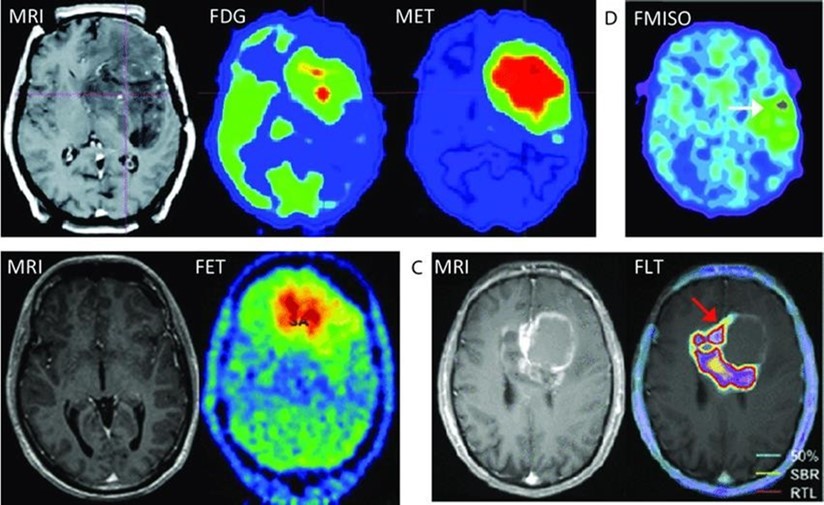

It is a non–invasive method. It can be used to monitor the chemical changes of tissues. We can simultaneously evaluate several metabolites. Two examples of where MRS is very helpful in the brain: The invasion of the tumor (Glioblastoma multiform (GBM) into the surrounding tissues, which is not clear in normal T2 images, but can be determined by MRS. By MRS, it is possible to distinguish two types of lesions that look similar to each other in normal MRI images (such as tumor recurrence and tumor necrosis after radiotherapy). MRS imaging has found wide applications in the field of cancer diagnosis. Among the fields of clinical application of MRS, we can mention the diagnosis (between normal and cancerous tissue, different types of cancer and neoplastic from non–neoplastic), designing the best treatment regimens for each patient, and monitoring the patient after treatment. MRS in tumors: In brain tumors, spectroscopy can determine the degree of malignancy. As malignancy increases, NAA and creatine decrease and choline, lactate and fat increase. Fat is seen in the necrotic parts of the tumor. Lactate concentration increases in rapidly growing tumors due to anaerobic glycolysis. Diagnosing tumor recurrence from the effects of radiotherapy: Increased choline is a marker for tumor recurrence. Changes due to radiotherapy usually decrease NAA, creatine and choline. If necrosis has occurred as a result of radiotherapy, fat and lactate can also be seen in the spectrum. Molecular imaging using spectroscopy Cerebral ischemia and infarction: When the brain suffers from ischemia, anaerobic respiration of glucose is used and lactate increases. Choline increases and NAA and creatine decrease. If it happens after ischemia, the fat signal is also seen. trauma: It is a useful method to assess the degree of nerve damage and predict the results. The clinical consequences are opposite to the NAA/Cr ratio, and the observation of lactate and fat indicates the seriousness of the condition. infectious diseases: decrease naa Inside the abscess, lactate, alanine, cytosolic acid and acetate increase. Alzheimer: In the advanced stages of Alzheimer's, NAA decreases and myo–inositol increases. MS: The increase of choline and lactate has shown that the increase of choline can be due to the increase of phospholipid as a result of breaking the myelin of the cell and the increase of lactate is due to the increase of the anaerobic respiration of the cell due to the increase of the cell metabolism. In addition, there is evidence of increased lipids, and most importantly, decreased NAA, which is caused by nerve damage. And recently, it has been found that glutamate and myoinositol levels increase in acute MS lesions. Parkinson: In most studies in Parkinson's disease, no changes in metabolites have been observed, only when Parkinson's has caused brain atrophy, a decrease in NAA in the basal ganglia has been observed (Figure 3, Figure 4, Figure 5, Figure 6).

Figure 3.Different spectra metabolites in different areas of the human body.

Different spectra metabolites in different areas of the human body.